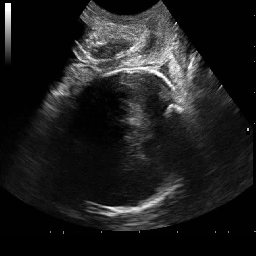

Pubic Symphysis and Fetal Head Detection (FH-PS-AoP): The FH-PS-AoP dataset [20] comes from the Pubic Symphysis–Fetal Head Segmentation Challenge, which deals with transperineal ultrasound imaging. It includes 2D B-mode ultrasound images from different regions of China, gathered with standard ultrasound machines. The dataset contains information about pregnant women between 18 and 46 years old. Annotation was conducted using Pair software and was performed by a group of seven annotators composed of two senior specialists and five undergraduates. The entire dataset contains 4,000 images for training and 700 for testing. For model training, the 4,000 training samples were divided into an ratio for training and validation to monitor potential overfitting. Lastly, the 700 test samples were used for performance evaluation.

Figure 4 and Figure 5 provide visual comparisons of segmentation masks generated by DAUNet and other competing methods on representative samples from both datasets. As illustrated in Figure 4, DAUNet produces more accurate and smoother boundary delineations, closely aligning with the ground truth annotations, even in challenging low-contrast regions or under partial occlusion. A similar performance can be observed in Figure 5, where proposed model accurately identify the pulmonary embolism regions. It is worth nothing that the proposed model achieve best performance in two different imaging modalities, consisting of different sized regions of interest and number of classes demonstrating a good generalization.

In practical clinical settings, medical images are often incomplete or degraded due to occlusions, artifacts, or limited fields-of-view. Therefore, a reliable segmentation model must be robust to missing spatial context and capable of inferring anatomical structures from partially observed inputs. To evaluate this critical property, we conducted a masking experiment using the FH-PS-AoP dataset. In this experiment, we systematically removed one quadrant from the input image, top-left, top-right, bottom-left, or bottom-right, and evaluated the performance of DAUNet compared to the baseline UNet.

The segmentation masks in third and fifth rows of Figure 7, further substantiate these findings. DAUNet consistently produces anatomically plausible segmentations of both the fetal head (green) and pubic symphysis (red), with minimal degradation even under 25% missing input. The output contours remain smooth, accurate, and well-aligned with ground truth boundaries. In contrast, UNet’s performance deteriorates noticeably, with fragmented or distorted segmentations, especially around the fetal head, as indicated by white arrows in the figure.